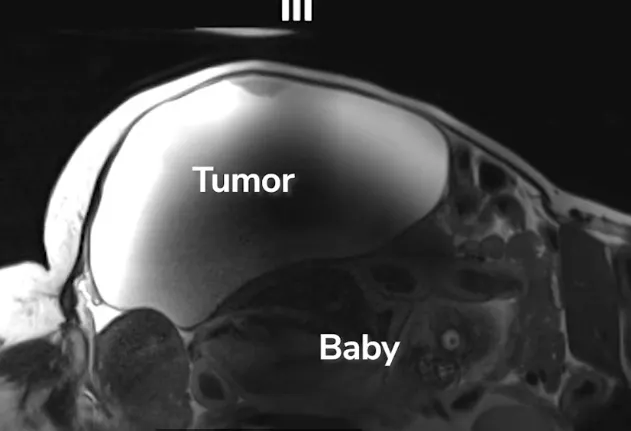

People inside other people...